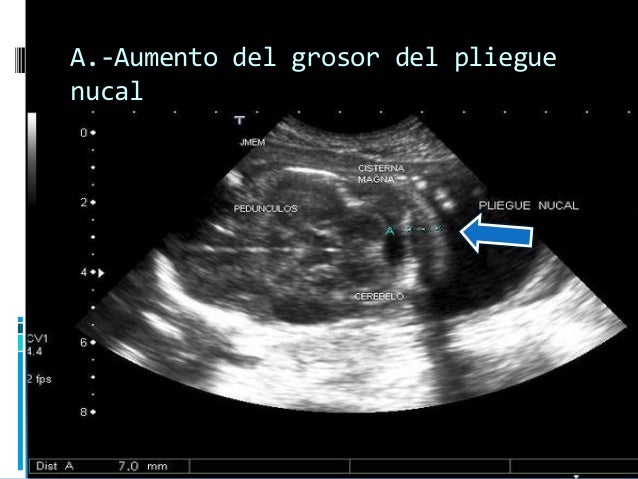

Si la prueba del pliegue nucal detecta translucencia nucal aumentada se recomienda realizar a la embarazada, entre las semanas 15 y de la gestación, una ecografía detallada para buscar otros marcadores ecográficos de cromosomopatías y descartar malformaciones cardiacas en el feto. Medida del pliegue nucal normal Los calipers se sitúan en el margen externo del hueso occipital (flecha) y en el margen externo de la piel nucal (flecha larga) 34 Pliegue nucal engrosado en un feto con trisomía 21 Pliegue nucal engrosado (cursores) La medida de 6 mm es elevada 35 Ventriculomegalia • Ventrículos de gran tamaño. Corresponde a la medida del pliegue nucal medido por ecografía cuando el feto tiene una posición neutra (es decir, está en horizontal respecto a la visión ecográfica, con la parte anterior del abdomen hacia arriba).